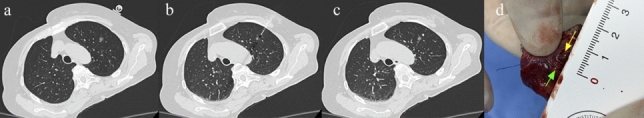

准确的术前定位对于小肺结节的手术切除至关重要,然而传统的ct引导下的钩线放置仍然依赖于手术人员和技术要求。这项前瞻性研究评估了机器人辅助导航系统在ct引导下术前肺结节钩线定位中的临床表现。该试验招募了60名患者,计划在定位后进行VATS。主要终点包括首次穿刺成功率、置针准确性、定位成功率、手术时间、穿刺次数、辐射剂量、并发症发生率,并根据病灶特征和患者体位进行亚组分析。首次穿刺成功率为100.0%,中位置针精度为5.7 mm (IQR 4.2-7.9)。94.8%的结节成功定位(55/58)。中位手术时间为16.6 min(14.0 ~ 22.9),中位辐射剂量为281.2 mGy·cm(227.1 ~ 365.8)。总并发症发生率为5.2%(3/58)。准确性在各亚组中是一致的,尽管下肺叶病变和俯卧位与较长的手术时间有关,俯卧位也增加了辐射暴露,但不影响准确性。这些发现证明了该系统的可行性、精确性和安全性,支持其标准化和改善胸外科术前定位的潜力。试验注册:注册号:https://www.chictr.org.cn/, TRN: ChiCTR2500095919,注册日期:2025年1月15日。

Accurate preoperative localization is critical for the surgical resection of small pulmonary nodules, yet conventional CT-guided hookwire placement remains operator-dependent and technically demanding. This prospective study evaluated the clinical performance of a robot-assisted navigation system for CT-guided preoperative hookwire localization of pulmonary nodules. The trial enrolled 60 patients scheduled for localization followed by VATS. Primary endpoints included first-attempt puncture success rate, needle placement accuracy, localization success rate, procedure duration, number of punctures, radiation dose, and complication rate, with subgroup analyses by lesion characteristic and patient positioning. The first-attempt puncture success rate was 100.0%, with an median needle placement accuracy of 5.7 mm (IQR 4.2-7.9). Localization success was achieved in 94.8% of nodules (55/58). The median procedure duration was 16.6 min (14.0-22.9), and the median radiation dose was 281.2 mGy·cm (227.1-365.8). The overall complication rate was 5.2% (3/58). Accuracy was consistent across subgroups, although lower lobe lesions and prone positioning were associated with longer procedure times, and prone positioning also increased radiation exposure, without compromising accuracy. These findings demonstrate the feasibility, precision, and safety of this system, supporting its potential to standardize and improve preoperative localization in thoracic surgery. Trial registration: Registry: https://www.chictr.org.cn/ , TRN: ChiCTR2500095919, Registration date: January 15, 2025.